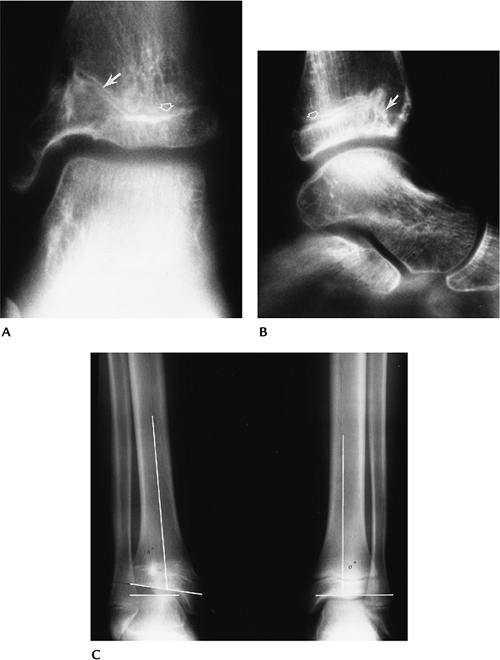

P.321

FIGURE 6-8 Prior Salter-Harris IV fracture of the distal tibia. AP (A) and lateral (B) radiographs demonstrate premature closure and angular deformity of the anteromedial growth plate (arrow). The physis remains open laterally and posteriorly (open arrow). Standing radiographs (C)

in a different patient with an old physeal fracture on the right and leg length discrepancy and angular deformity of the articular surface (lines). |